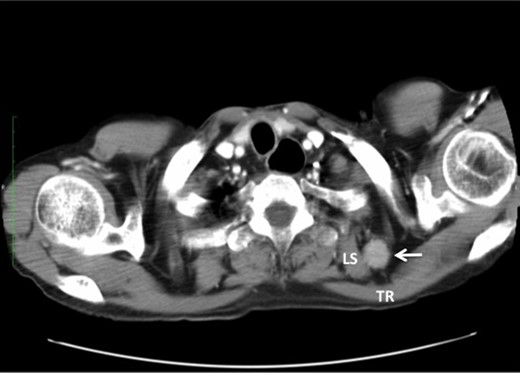

We have had three cases of this unusual LNM from cancer of the thoracic esophagus to date. Clinicopathological characteristics and survival are presented in Table 1. This unusual LNM developed after esophagectomy in two patients (cases 1 and 2, Fig. 2) and was found at presentation in a third patient (case 3, Fig. 3).

Metastasis of the supraclavicular nodes (SCNM), the nodes located between TR and LS (arrow) (A), and the axillary nodes (ANM) (B) developed 4 months after esophagectomy.